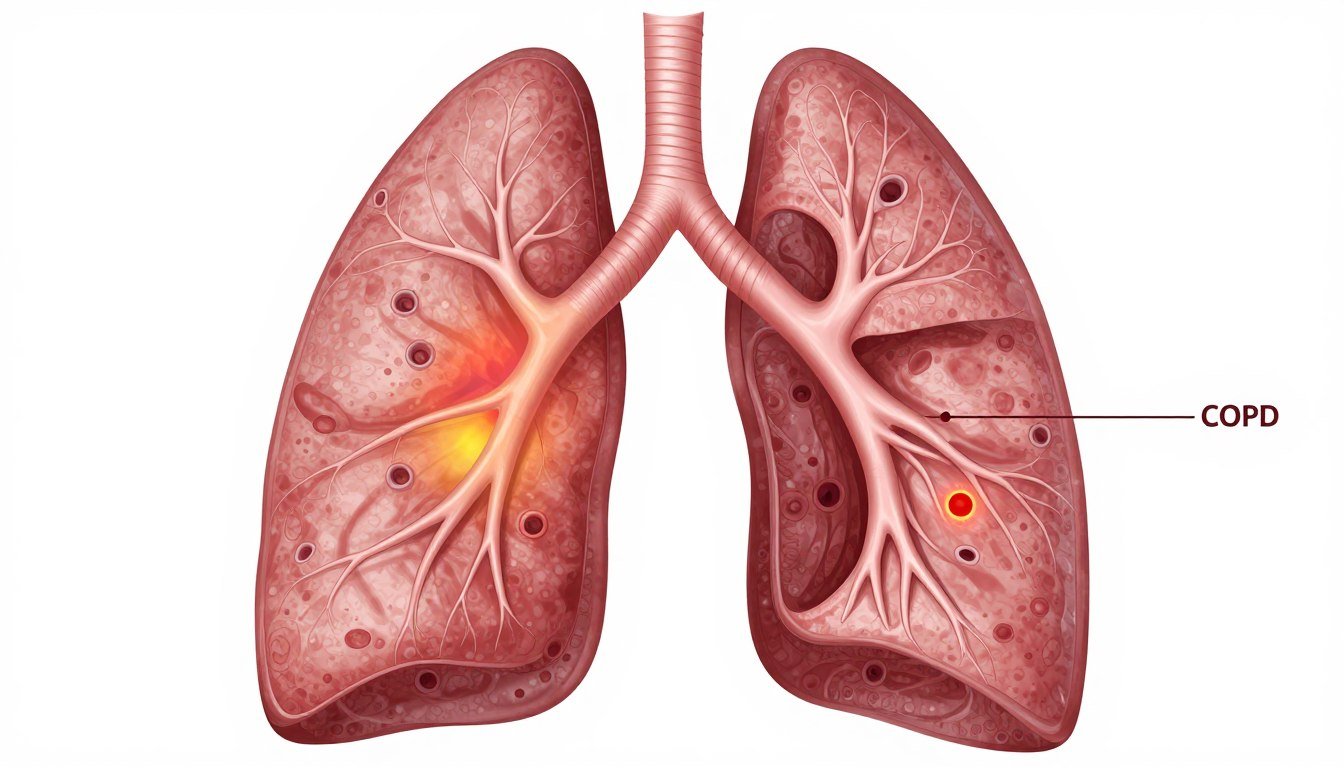

How COPD Affects Your Lungs

In healthy lungs, air flows freely through airways into air sacs. These delicate structures facilitate oxygen exchange with the bloodstream.

COPD damages this intricate system. Airways become inflamed and narrowed while air sacs lose their ability to expand and contract properly.

The result is trapped air in the lungs. This phenomenon makes it increasingly difficult to breathe out completely.

Medical Insight: Unlike asthma, COPD involves permanent lung damage. The condition is chronic and progressive, requiring long-term management strategies.